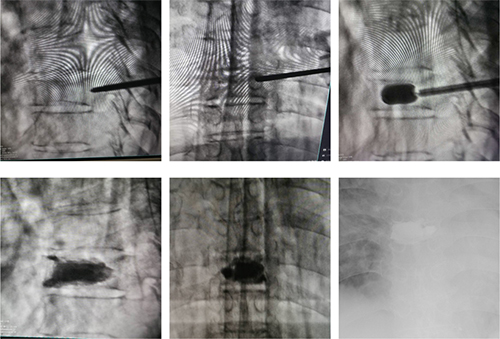

术中透视及术后患者腰椎正位X线检查

6月中旬,在局部浸润麻醉下王甫主任及医护团队为患者实施了T8骨折经皮椎体成形术,仅用15分钟便快速完成了手术。手术效果立竿见影,病人疼痛立即缓解,憋喘明显减轻,血氧升至90%以上,患者术后当晚睡了受伤之后的第一个整觉。第二天,患者即可在搀扶下站立行走,饮食、呼吸、睡眠及活动能力很快恢复到受伤前的状态。术后第三天顺利出院,患者及家属非常满意,再三对医护人员表示感谢。